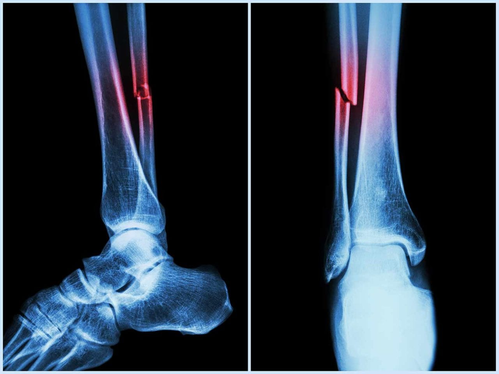

ऑस्ट्रेलिया आणि कॅनडाच्या शास्त्रज्ञांनी एक नवीन अल्गोरिदम तयार केला आहे, जो हाडांच्या सामान्य तपासणीदरम्यानच हृदयविकार आणि हाड तुटण्याच्या धोका ओळखू शकतो. सिन्हुआ न्यूज एजन्सीच्या रिपोर्टनुसार, ही तंत्रज्ञान ऑस्ट्रेलियातील एडिथ कोवान युनिव्हर्सिटी आणि कॅनडाच्या युनिव्हर्सिटी ऑफ मॅनिटोबा येथील वैज्ञानिकांनी संयुक्तपणे विकसित केली आहे. यामुळे वयोवृद्ध लोकांच्या आरोग्याचे पूर्वानुमान लावून त्यांचे आरोग्य सुधारण्यात मदत होईल.

या प्रणालीची खास गोष्ट म्हणजे ती रीढेच्या हाडांचा स्कॅन (VFA – Vertebral Fracture Assessment) बघून पोटातील प्रमुख धमन्यांतील कॅल्सिफिकेशन (AAC – Abdominal Aortic Calcification) ओळखते. AAC ही स्थिती हृदयविकाराचा झटका, स्ट्रोक आणि पडण्याच्या धोक्यांशी संबंधित असते. यापूर्वी तज्ज्ञांना AAC ओळखण्यासाठी ५–६ मिनिटे लागायची, पण हे नवीन तंत्रज्ञान हजारो प्रतिमा एका मिनिटापेक्षा कमी वेळात तपासू शकते. यामुळे मोठ्या प्रमाणावर आणि वेगवान तपासणी शक्य होणार आहे.

एडिथ कोवान युनिव्हर्सिटीच्या संशोधक कॅसेंड्रा स्मिथ यांच्या मते, हाडांची नियमित तपासणी करवणाऱ्या ५८% वृद्ध महिलांमध्ये मध्यम ते जास्त AAC आढळले, पण त्यांना हृदयविकाराच्या या धोक्याची कल्पना नव्हती. त्यांनी सांगितले की, महिलांना अनेकदा हृदयरोगाची तपासणी करून घेणे शक्य होत नाही आणि म्हणूनच त्यांच्यावर उपचार होत नाहीत. या आजाराची लक्षणे स्पष्ट नसल्यामुळे तो अनेक वेळा लक्षात येत नाही. पण ही नवी प्रणाली हाडांची तपासणी करतानाच हे धोके स्पष्ट करते.

संशोधक मार्क सिम यांच्या मते, AAC हे केवळ हृदयरोगाचे संकेत देत नाही, तर ते पडणे आणि हाड तुटणे यासारख्या घटनांचेही मुख्य कारण ठरते. त्यांनी सांगितले की हे नवीन अल्गोरिदम जुन्या पद्धतींपेक्षा अधिक अचूक माहिती देते. ते म्हणाले, “आम्ही पाहिले की AAC जितके जास्त असेल, तितका व्यक्तीचा पडण्याचा आणि हाड तुटण्याचा धोका जास्त असतो. डॉक्टर सामान्यतः याकडे दुर्लक्ष करतात, पण हे नवे तंत्रज्ञान ही उणीव भरून काढते.

परिणामतः, आता हाडांची तपासणी करतानाच रुग्णाच्या धमन्या व हृदयाच्या आरोग्याची माहिती मिळू शकते. त्यामुळे हाडं कमकुवत असलेल्या रुग्णांमध्ये धोका आधीच ओळखून वेळेत उपचार करता येऊ शकतात.